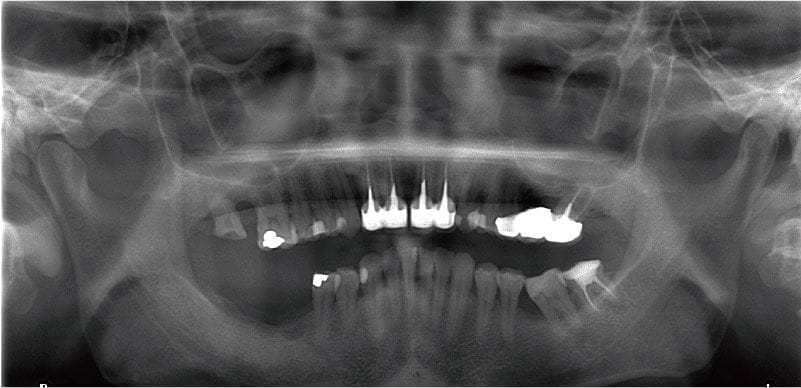

牙周病治療前,先透過環口式X光片完整檢查牙齒狀況

通常在初診或是定期檢查時,除了局部不適的位置外,我會做完整口內檢查。此外,「環口式全口X光片」是快速篩檢全口狀況的最佳利器,這樣我們可以紀錄很多需要的資訊,例如:有無蛀牙或牙齒缺損、缺牙區域、牙齒排列、曾經做過假牙或植牙的位置、牙齒位移的狀態、篩檢牙周狀態,以及可能的其他發現。

圖示:Mr.Lin環口式X光片,診斷為全口牙周病

針對牙周病,從環口式X光片初步檢測出齒槽骨流失的狀況,並配合部分牙齒牙周囊袋的檢測,我們可以由此診斷出Mr.Lin也有全口牙周病需要治療。